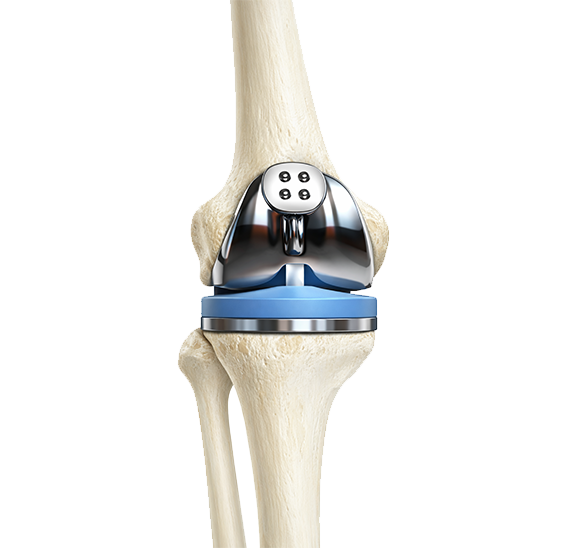

연골이 닳아 없어질 정도로 진행된 퇴행성 관절염은 비수술적 치료로는 더 이상 통증 조절이나 기능 회복이 어려워 수술적 치료를 고려해야 합니다.

하지만 나이가 70세 이상이거나, 무릎관절염이 3~4기 정도로 많이 진행된 경우에는 인공관절 수술을 고려해봐야합니다.

3D 프린팅 기술을 이용한 PSI(Patient Specific Instrument) 인공관절 수술은 기존의 인공관절 수술의 단점과 한계점을 보완한 최신지견의 수술법으로 1mm 오차도 허용하지 않고, 무릎 건강을 되찾습니다.

PSI란 환자분의 MRI 혹은 CT 영상 이미지를 3D로 구현하여 환자분 개인별 해부학적 특성에 맞게 3D 프린팅으로 1mm 오차 없이 제작하는 환자맞춤형 인공관절 수술기구입니다. 수술 시 정밀한 해부학적 절삭 각도 및 범위를 제공해 정확하고 빠른 수술의 진행이 가능합니다.